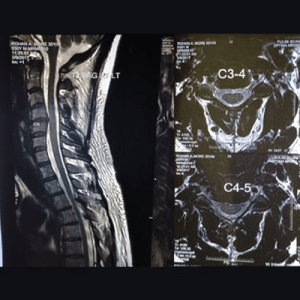

A 30-year-old male patient presented in March 2017 with complaints of neck pain, swelling, and restricted mobility over the past few days. An MRI of the entire spine revealed a diffuse posterior bulge at the C4-C5 disc, with broad-based posterocentral and left paracentral protrusion, along with mild prediscal osteophytes. These findings were compressing the anterior subarachnoid space and indenting the left exiting nerve root. The MRI images showed the following findings, as seen in Figures 2 and 3:

Figure 2: Diffused posterior bulge of C4-5 disc with broad-based posterocentral and left paracentral protrusion with mild peridiscal osteophytes compressing the anterior subarachnoid space and indenting left exiting nerve root

Figure 3: Reveals diffuse posterior bulge of D3-4 disc & D4-5 disc indenting anterior subarachnoid space. Focal ligamentum flavum hypertrophy is seen at D3-4, D4-5, and D10-11 levels, indenting the posterior subarachnoid space. L5-S1 disc is dessicated and reveals diffuse posterior bulge with posterior annular tear indenting thecal sac